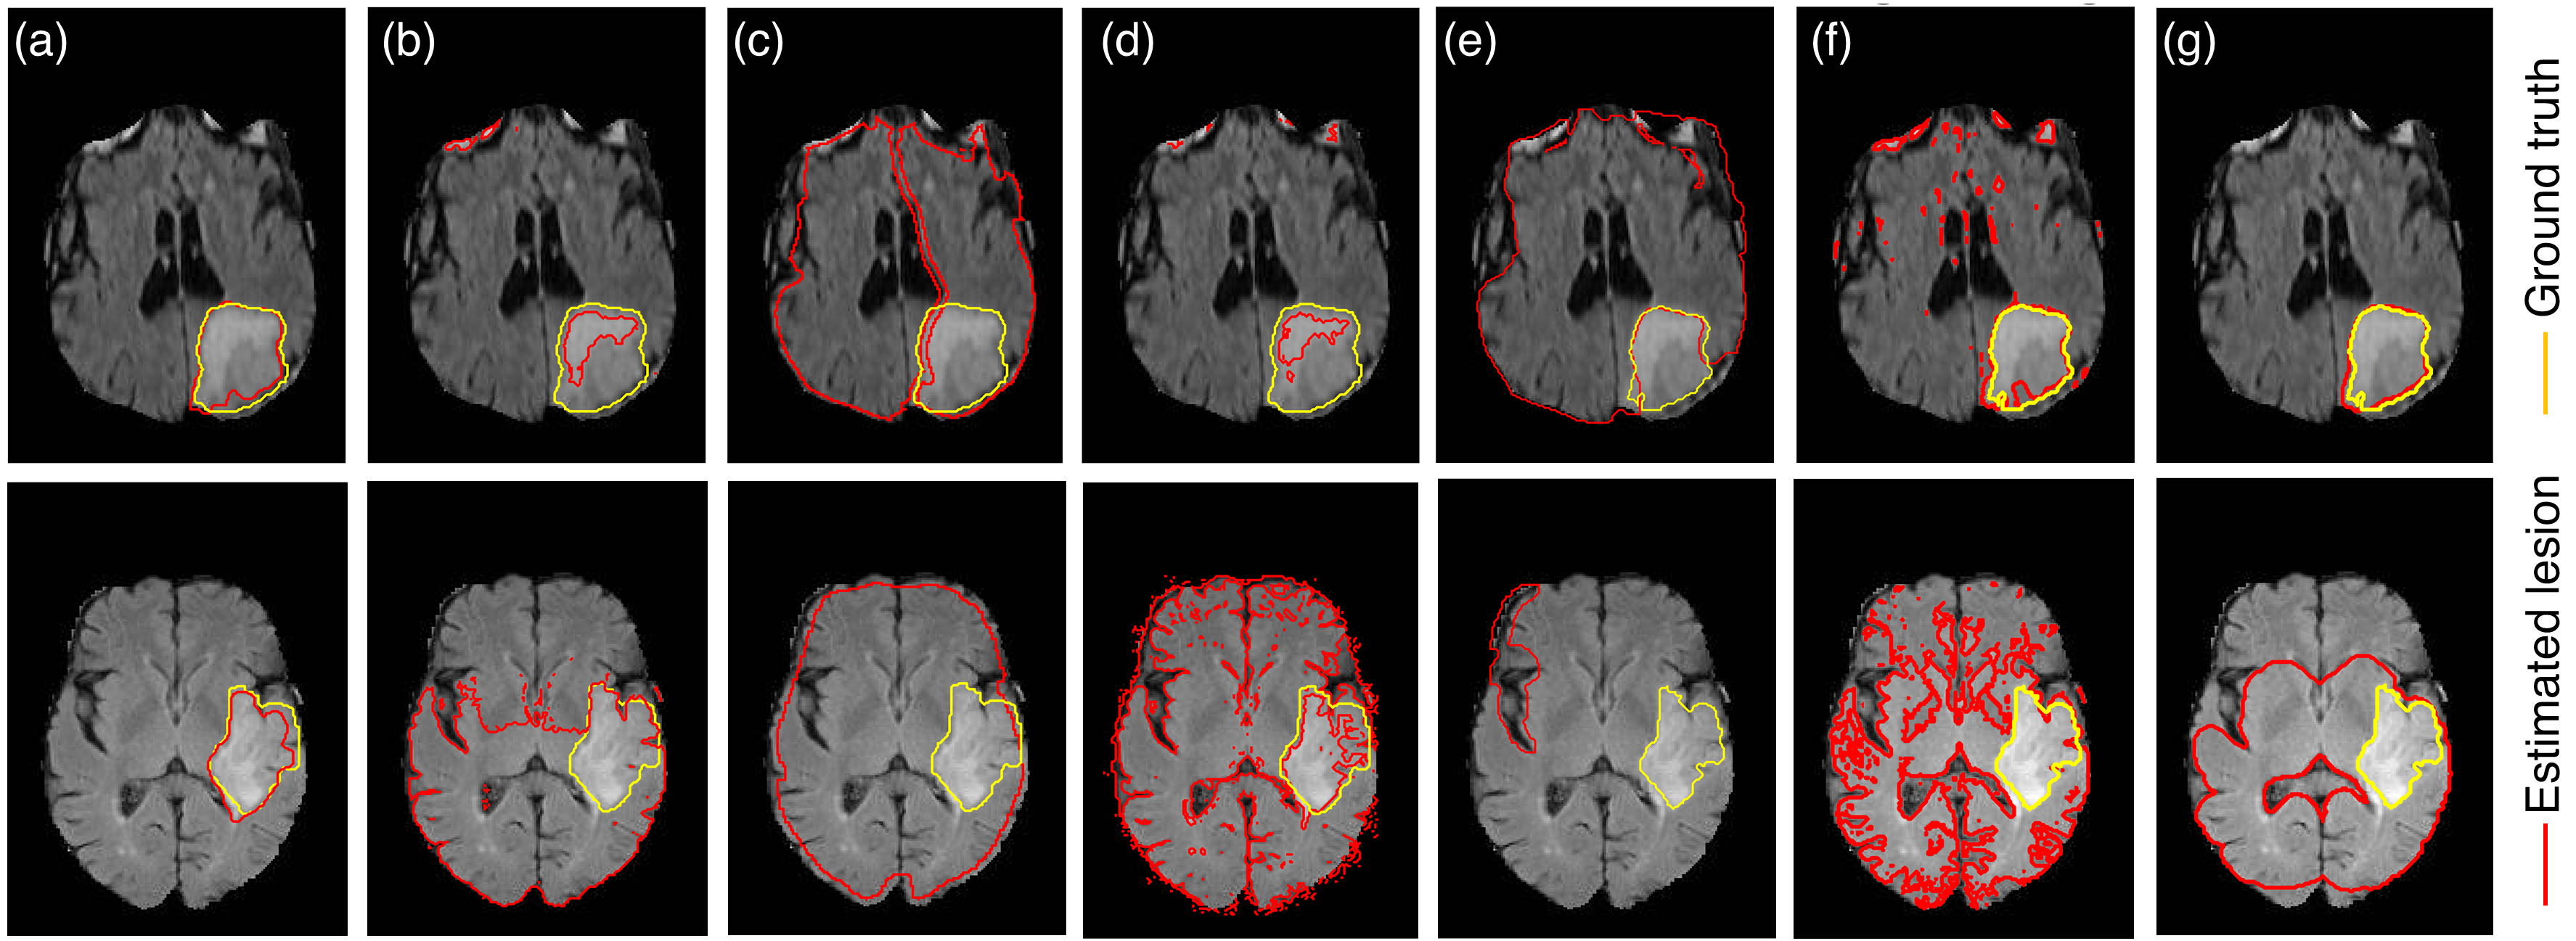

Refer to caption

Figure 6: Segmentation results of different unsupervised approaches for the segmentation of brain tumor on HG (top row) and LG (bottom row) glioma. (a) The proposed method (b) mean shift (c) normalized cuts (d) blobworld (e) hierarchical image segmentation (f) GMM and (g) spatially constrained GMM.

Segmentation results of a representative HG and LG glioma are presented in the top and bottom rows of Figure 6, respectively. The segmentation results for the present approach is shown in Figure 6(a) followed by rest of the unsupervised segmentation methods in Figures 6(b)-(g). Note that some of the methods such as mean shift (Figures 6(b)) required setting the bandwidth and kernel function whereas completely unsupervised methods such as normalized cuts (Figures 6(c)) failed to converge. Clearly, the present method performs better as compared to the unsupervised methods tested. The overall performance of the present algorithm is 78% and 75.6% on the Dice score for the BraTS 2013 and BraTS 2015 dataset, respectively. The 95% Hausdorff distance for the two datasets are 13.61 and 14.05, respectively. Based on the segmentation results, we also note that the present approach significantly minimizes oversegmentation as compared to most of the segmentation approaches reported in Figure 6. This is due to the TV regularization in the max-flow formulation that penalizes the oscillations in the pixel intensity due to random noise. We also compare the computational cost of the unsupervised algorithms that converged within a reasonable time and is summarized in Figure (7). Although our method is slower than k-means and GMM, it performs reasonably fast as compared to mean-shift and spatially constrained GMM.